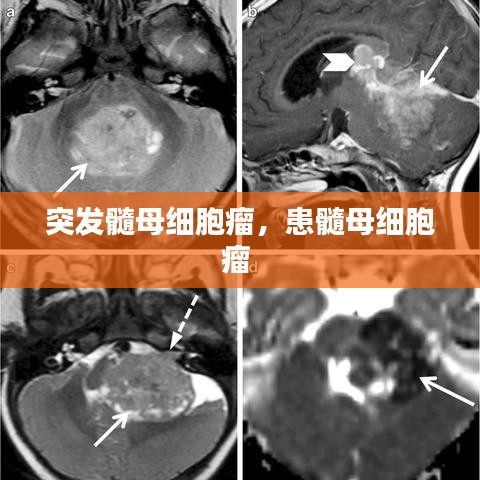

- 影像学检查:包括CT扫描、MRI和PET扫描,这些检查可以帮助医生确定肿瘤的位置、大小和性质。